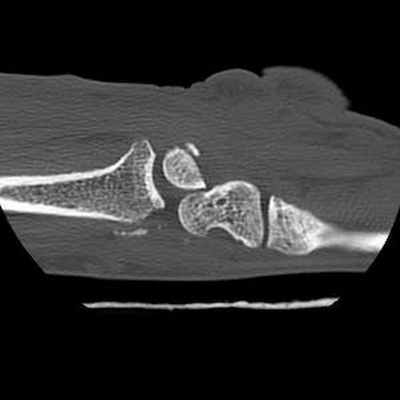

Трансладьевидно-перилунарный вывих запястья III-его типа

Трансладьевидно-перилунарный вывих запястья (перелом ладьевидной кости в виде основной сагиттальной линии, с образованием двух сильно смещенных фрагментов; проксимальный фрагмент остается в нормальном соотношении с полулунной костью; разъединение костей первого и второго ряда запястья).

Наличие мелких костных фрагментов вокруг трехгранной кости вместе с отрывными переломами; смещение кзади трехгранной кости.

Оскольчатый перелом шиловидного отростка лучевой кости.

Локтевая кость цела.